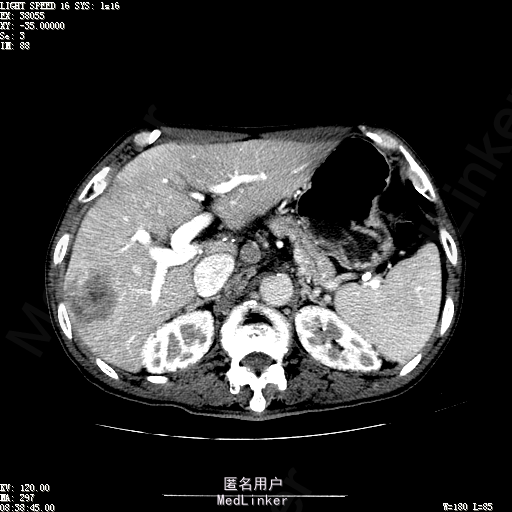

查体:体温36.3℃,脉搏76次/分,呼吸18次/分,血压120/80mmHg。神志清晰,肝病面容,皮肤粘膜颜色正常无黄染,全身皮肤未见皮疹、瘀点及紫癜,肝掌阳性,未见蜘蛛痣,浅表淋巴结未触及。巩膜无黄染,结膜正常。双肺呼吸音清,无胸膜摩擦音。心率:76次/分,心律齐,心音正常,无杂音,无心包摩擦音。腹平坦,无腹壁静脉曲张,未见胃肠型及蠕动波,双侧腹股沟可见手术瘢痕,脐部正常。触诊:无压及痛反跳痛,无腹肌紧张,无腹部包块。肝脾肋下未触及,Murphy征阴性,肾未触及,移动性浊音阴性。肝肾区叩击痛阴性,无脾区叩击痛。听诊:肠鸣音正常,4次/分,无气过水声。脊柱无侧弯,脊柱活动度正常,棘突正常,四肢正常,关节正常,无下肢水肿,无下肢静脉曲张,无杵状指趾。扑翼样震颤阴性。 门诊化验ALT9U/L,AST21U/L,HBVDNA<1.0E+03IU/mL,HBsAg1138IU/mL,WBC6.2x10^9/L,RBC3.92x10^12/L,PLT167x10^9/L,AFP28.95ng/ml,AFU 29U/L,彩超示肝右叶肝回声,大小约5.1*3.5cm,Fibroscan:脂肪变:163硬度10.8。 CT如下图

诊断:1、乙肝肝硬化 活动性 代偿期 原发性肝癌 2、胃溃疡 3、十二指肠球部溃疡 处理:血管介入治疗:手术者术前查看患者相关情况:化验回报:血细胞分析(五分类):*白细胞计数 8.1 10^9/L、*红细胞计数 4.00 10^12/L↓、*血小板计数 202.0 10^9/L、*血红蛋白 136 g/L,肝功酶谱:*丙氨酸氨基转移酶 5 U/L、天门冬氨酸氨基转移酶 22 U/L、*白蛋白 37.6 g/L、*总胆红素 17.8 umol/L,肾功能检测:*尿素 5.79 mmol/L、*肌酐 67.1 umol/L,凝血五项:凝血酶原时间 10.7 秒↓、凝血酶原百分活动度 93.3 %,甲胎蛋白测定:甲胎蛋白 30.30 ng/mL↑。患者病情平稳,今日术前准备,签署相关文件。 手术简要经过:患者平卧位,以右侧腹股沟区为中心常规消毒、铺巾、利多卡因局麻。改良Seldinger法逆行穿刺右侧股动脉成功,置入5F血管鞘。经血管鞘造影,见髂外动脉明显迂曲,经鞘送入超滑导丝,退出原5F血管鞘,换入5F长25厘米血管鞘。沿导丝送入肝管,将管头送入腹腔干,进一步送至肝右动脉。经正位、右前斜30°造影,明确肝右叶膈顶一处较大肿瘤染色,S5段一处较小肿瘤染色。以微导管超选S6段肝动脉干,经多角度造影明确为肿瘤供血动脉,注入混悬液(碘化油10毫升+雷替曲塞2毫克)3毫升,明胶海绵颗粒1/12支。再以微导管超选S7段肝动脉干,造影明确为肿瘤供血动脉,注入混悬液2毫升,明胶海绵颗粒1/20支。再以微导管超选S8段分支,造影明确为肿瘤供血动脉,注入混悬液2.8毫升,明胶海绵颗粒1/12支。再以微导管超选S5段肝动脉分支,造影明确为较小肿瘤供血动脉,注入混悬液0.8毫升,明胶海绵颗粒1/30支。退出微导管。经肝右动脉注入奥沙利铂100毫克。退出肝管。拔出血管鞘,局部压迫5分钟。加压包扎。